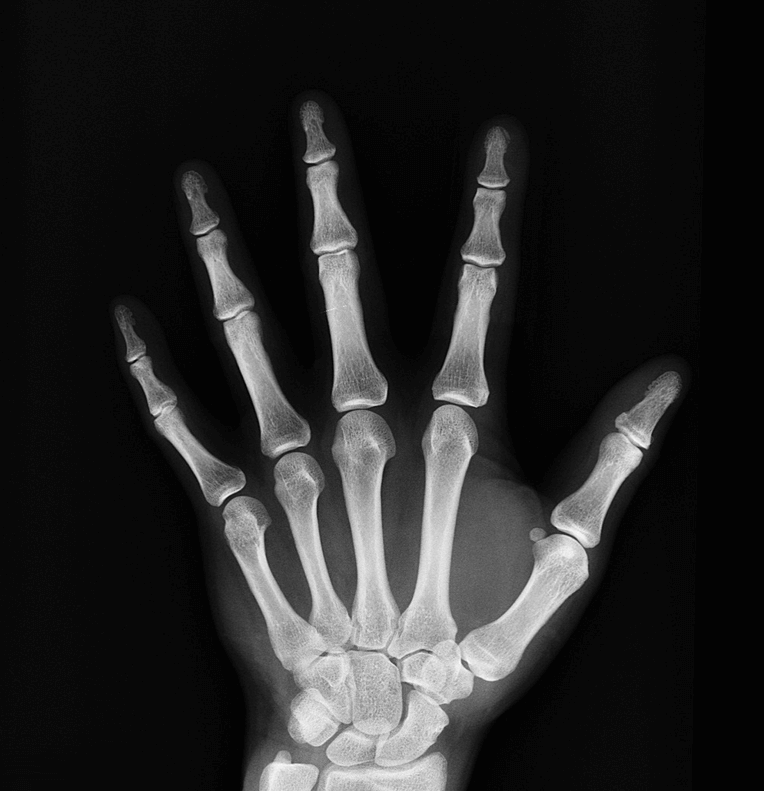

7. 성장지연

성장기에 있는 어린이, 청소년의 경우 뼈가 충분히 석회화되어야 몸을 지탱할 수 있게 됩니다. 하지만 칼슘부족증상으로 뼈나 치아의 석회화가 불충분하게 이루어지면 성장이 지연되기도 하며, 근골격계의 형성이 제대로 이루어지지 않을 수 있습니다.